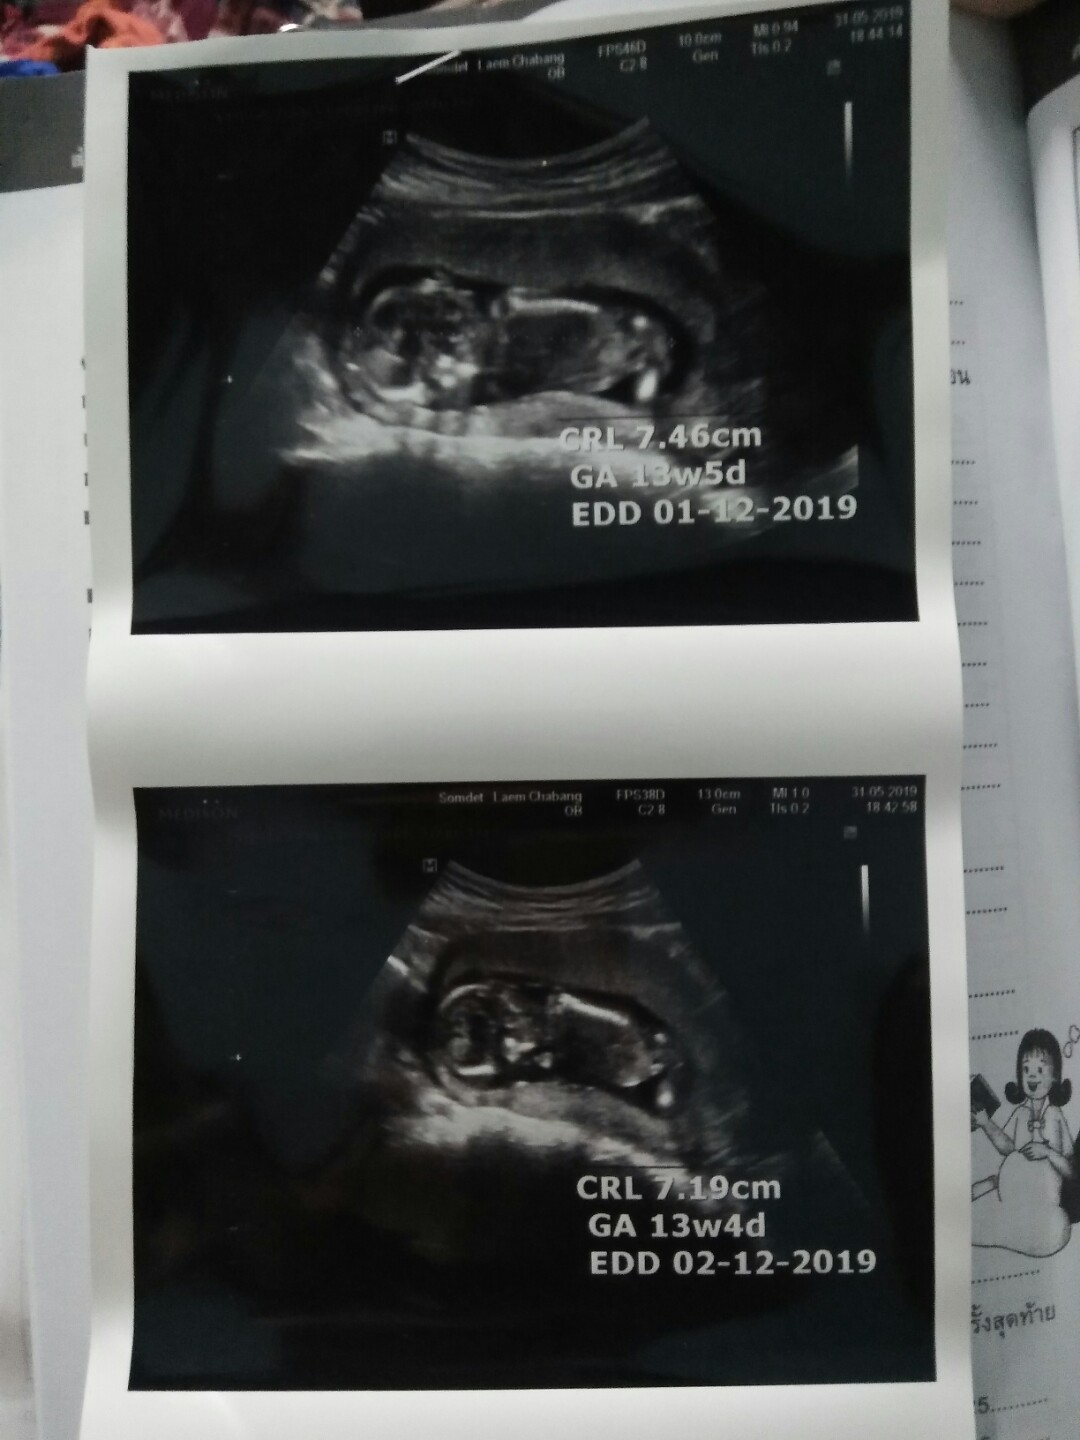

ตอนนี้15+2แล้วจ้า กำหนดคลอดประมาน25ธันวา จ้า